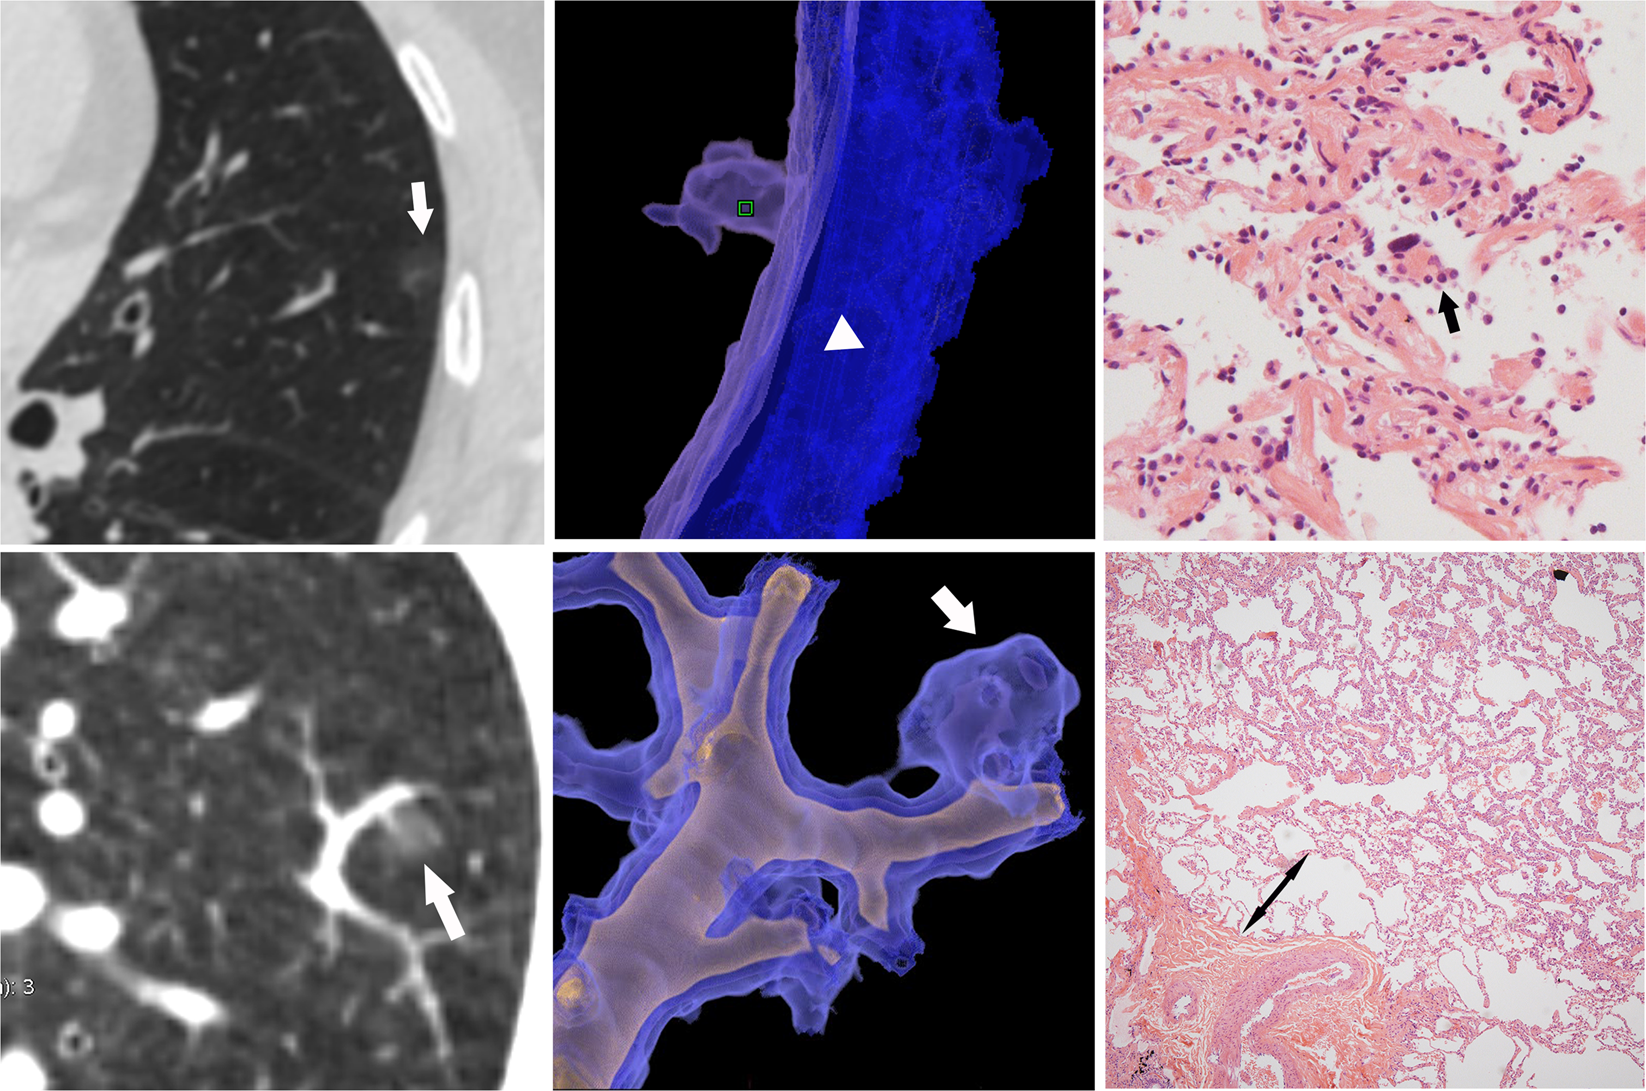

Figure 2

(a∼c) AAH in a 58-year-old woman. (a) Axial CT image shows the nodule is located in the upper lobe of the left lung (white arrow), with an maximum diameter of 6 mm. The maximum CT attenuation is low (−708HU) which suggested benign character. (b) Reconstructive CT image demonstrates the pGGN is close to pleura without pleura invasion. (c) High-power photomicrograph (Hematoxylin-Eosin, 100×) shows the proliferation and slight atypicality of epithelial cells (black arrow) along the alveolar space, and the cells are closely arranged with each other without any overlap and extrusion. (d∼f) AIS in a 49-year-old man. (d) Reconstructive CT image shows the pGGN (white arrow) close to a pulmonary vessel but there is a small gap with the adventitia. The maximum diameter is 6 mm, and the maximum CT value is −619HU. (e) Volume rendering image shows the vessel walking naturally with dilated and wrapped around. (f) Photomicrograph of a histologic specimen (Hematoxylin-Erosin, 40×) shows there is a space of normal lung parenchymal structure between the nodule edge and the vessel adventitia. (double-sided arrow).